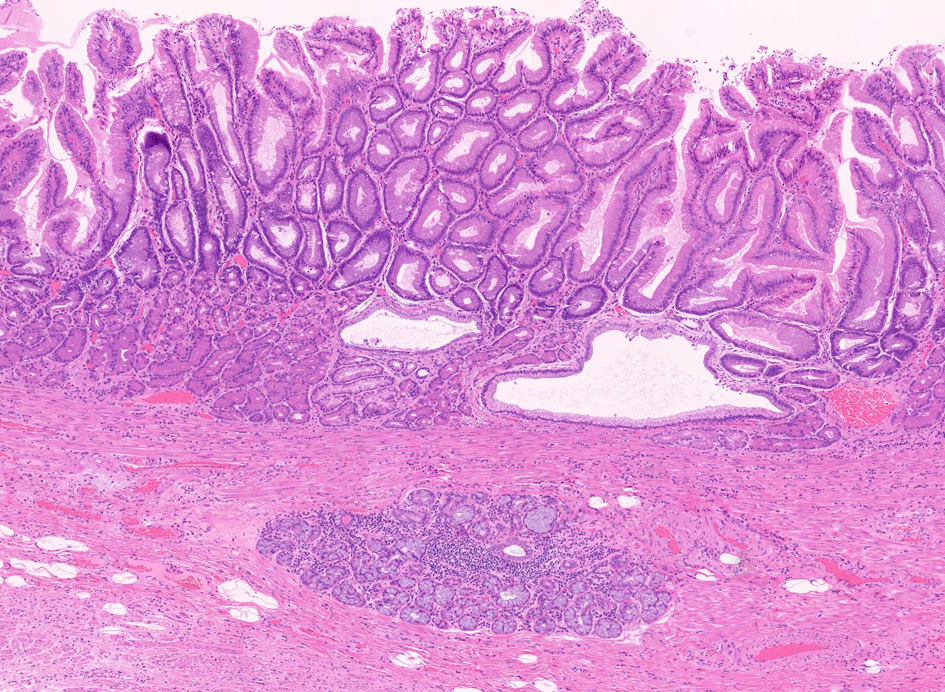

生検・手術での診断

1. 固有食道腺と導管が円柱上皮部位に存在する確定診断

2. 円柱上皮下の粘膜筋板二重化:かなり確実な所見,8割はあたり

固有食道腺(Esophageal Glands Proper:EGP)とは何か

EGPは常に扁平上皮から誘導されてできる腺で, その存在は必ず一度は粘膜内に扁平上皮があったという印であり食道固有の構造である。

扁平上皮島連続切片の観察では,すべての扁平上皮島は固有食道腺と導管を介して結合している

固有食道腺の開口部は必ず扁平上皮で囲まれており, 食道腺の上皮が進展しBarrett上皮ができるとする由来説は誤りである。